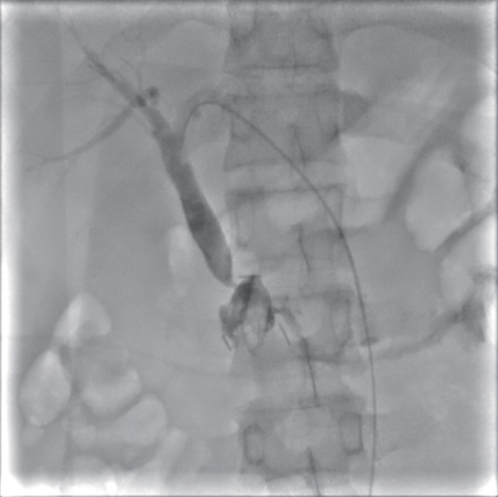

Successful treatment of biliary fistula after Beger surgery by oral choledochoscopy-assisted percutaneous-endoscopic rendezvous technique: A case report

Yuxin WANG, Weigang GU, Zheng JIN, Xiaofeng ZHANG

2025, 41(2): 333-336. DOI: 10.12449/JCH250220

Abstract(861) HTML (246) PDF (4794KB)(49)

Abstract:

Duodenum-preserving pancreatic head resection, also known as Beger surgery, has a high incidence rate of bile duct injury after surgery, while the treatment modality for bile duct injury depends on the severity of the injury, and endoscopic therapy is often challenging in case of severe bile duct injury. Recently a patient with biliary fistula after Beger surgery was admitted to Affiliated Hangzhou First People’s Hospital, Westlake University, and successful diagnosis and treatment were achieved through oral choledochoscopy-assisted percutaneous-endoscopic rendezvous technique.